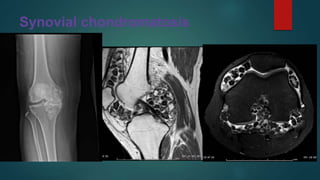

Synovial chondromatosis

• #93 There are numerous similar-sized intra-articular loose bodies of variable signal intensity, some of them are showing intermediate to high signal intensity that is of cartilage.  Others have low signal intensity at the periphery, which represents ossification. The joint capsule is distended with a little fluid and these numerous loose bodies Synovial chondromatosis (osteochondromatosis or synovial chondrometaplasia) also known as Reichel syndrome, is a disorder characterised by loose cartilaginous bodies which may, or may not be calcified or ossified. It is classified under two main types: primary synovial chondromatosis: predominantly monoarticular disorder of unknown aetiology secondary synovial chondromatosis: resulting in intra-articular loose bodies from causes such as trauma, osteoarthrosis and neuropathic arthropathy